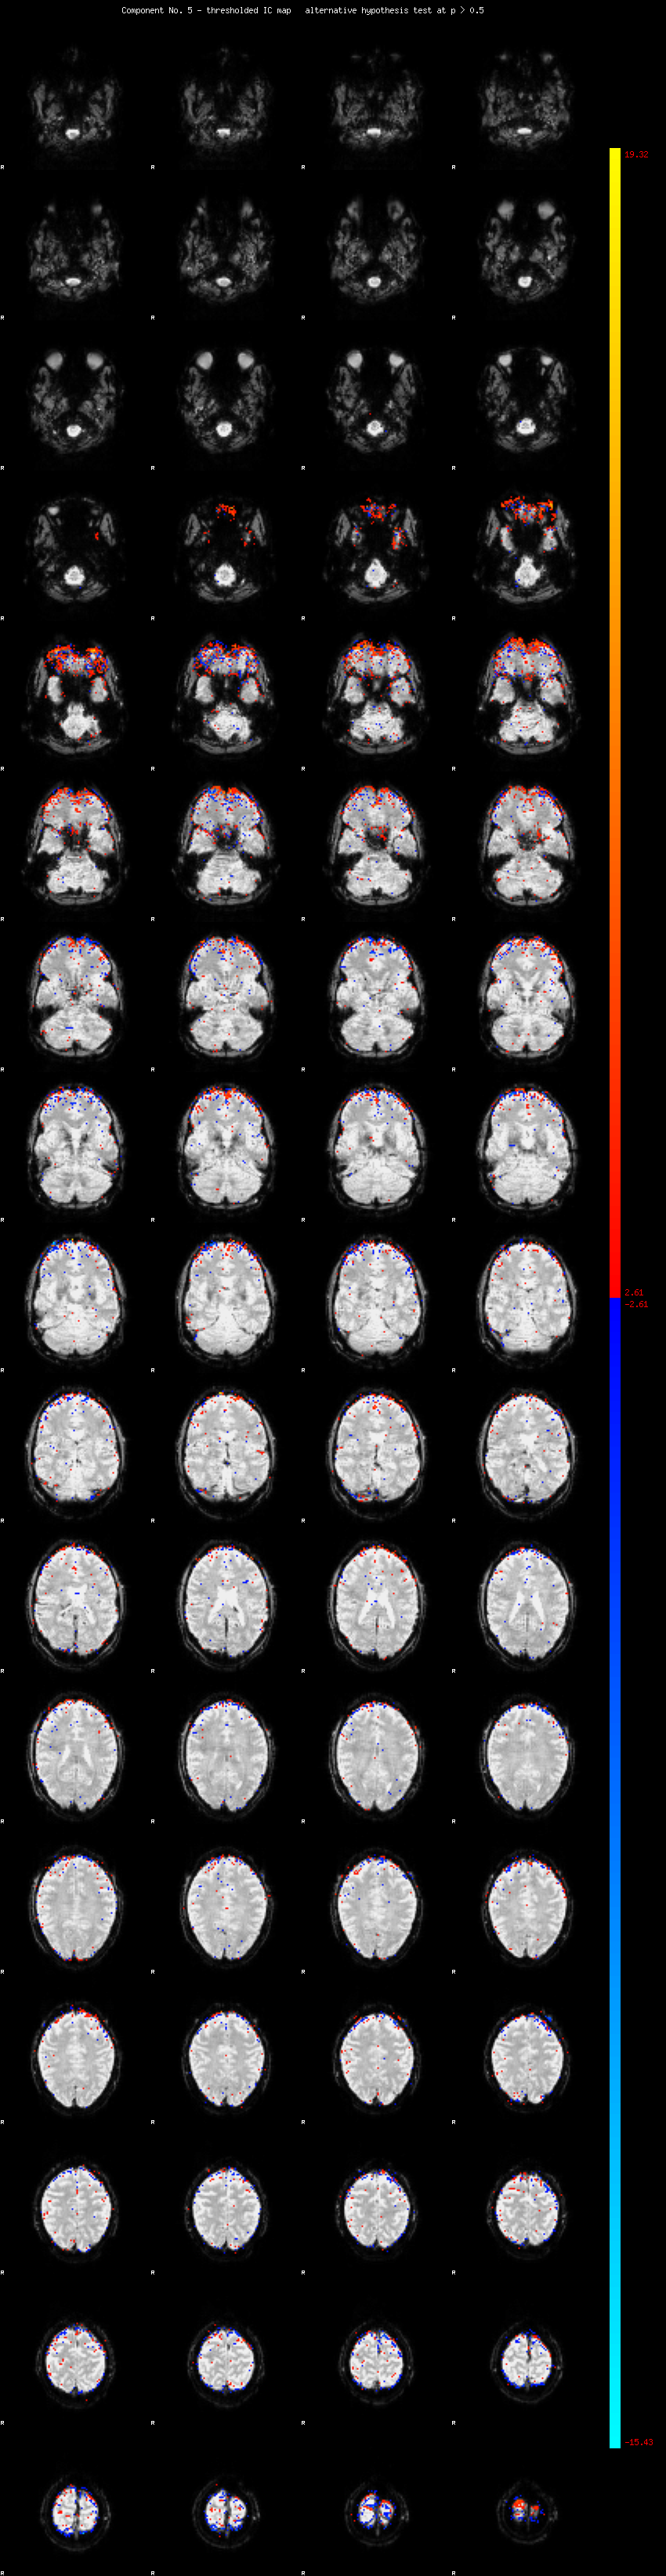

MELODIC Component 5

2.62 % of explained variance;     1.73 % of total variance